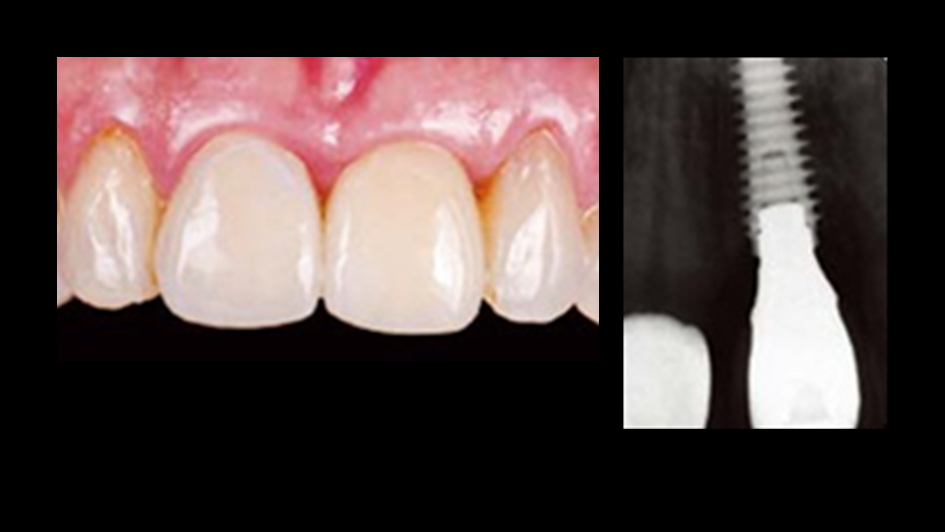

Clinical case: Replacement of fractured central incisor (#11) with immediate implant

& Root Membrane Technique

- Courtesy of Dr. Miltiadis Mitsias, Greece -

AnyRidge, Root Membrane Technique, retrospective study, long-term study, immediate implants, bone resorption, bone preservation, Dr. Miltiadis Mitsias,survival, success, maxillary anterior, single replacement

AnyRidge implant system, Root Membrane kit

The Root Membrane Technique: A retrospective clinical study with up to 10 years of follow-up./Implant Dent. 2018 Oct;27(5):564-574

https://www.ncbi.nlm.nih.gov/pubmed/30161062